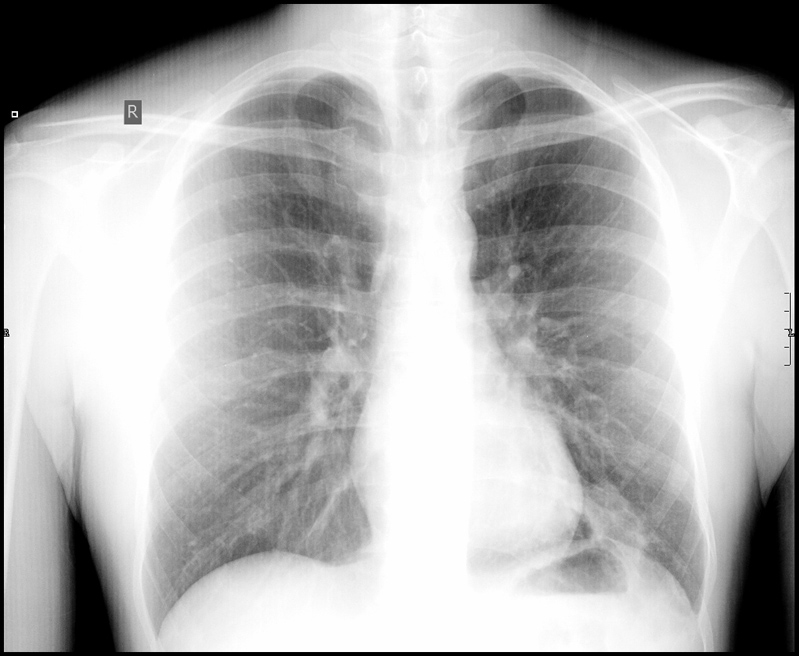

x-ray

well this is a first, all of the photos that i've posted on this blog have been taken by me except this one. if you haven't read about it already - this is from when i went to south africa and was hospitalised with pneumonia. in my ignorance i thought that pneumonia was only something that affected older people. when they were a bit too cold. turns out my ignorance wasn't that uncommon as the most frequent response when i told people was "how the fuck do you go to africa and get pneumonia?!". well, i was wrong and somehow picked up a bug that infected my lung. bugger. i was in for five days and as a leaving present they gave me antibiotics and digital copies of my x-rayed chest - just what i wanted. this was actually the second x-ray which the doctor said showed a reduction in the infection so i was free to be discharged. if this is a reduced infection you can imagine my first x-ray must have looked pretty severe.